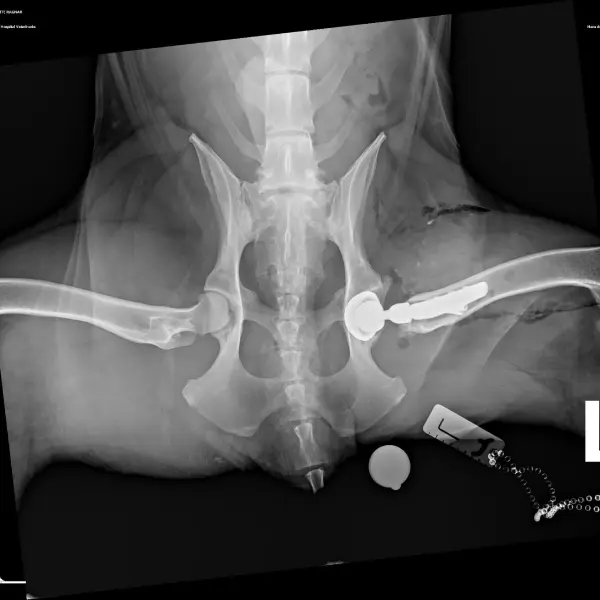

El diagnóstico de la displasia de cadera generalmente se alcanza a través de un completo examen ortopédico y con la realización de un estudio radiológico de las caderas bajo sedación o anestesia general. En este último los hallazgos pueden ser variables, desde incongruencia articular, hasta presencia de signos de degeneración articular (artrosis) como puede ser la deformidad coxofemoral y la aparición de osteofitosis (depósitos anormales de hueso) en la articulación.

- Sinfisiodesis púbica juvenil: es un procedimiento que se puede realizar en edades tempranas (hasta las 20 semanas de vida) en pacientes con presencia de laxitud articular detectada tanto en la exploración ortopédica como en un estudio radiológico específico de distracción (PennHip). Consiste en provocar la fusión prematura de la sínfisis de crecimiento púbica con el objetivo de modificar el crecimiento de la pelvis generando una mayor cobertura acetabular de las cabezas femorales, lo que permite mejorar la estabilidad articular y reducir la laxitud presente. La forma de conseguir la fusión de la sínfisis es empleando la electrocoagulación o colocando implantes quirúrgicos. Como antes de los 5 meses de edad normalmente no han aparecido signos clínicos y la indicación de esta técnica es a partir de la evaluación de la laxitud articular, puede considerarse una técnica quirúrgica profiláctica.

- Triple / Doble osteotomía pélvica (TOP / DOP): se trata de un procedimiento que se puede plantear en pacientes en crecimiento de hasta 10 meses de edad aproximadamente dependiendo de la raza o tamaño final estimado del perro. El objetivo de la cirugía es mejorar la congruencia y estabilidad de la articulación coxofemoral. Consiste en la realización de tres o dos cortes (osteotomías) controlados de la pelvis, para estabilizar mediante una placa especial el fragmento acetabular en una nueva posición donde conseguir una mayor cobertura de la cabeza femoral. Es una técnica que solo se puede utilizar en pacientes con laxitud articular pero sin remodelación articular ni signos de osteoartrosis.